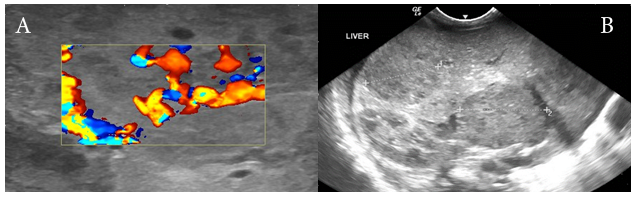

On day 30 of life baby started to show red papular lesions over palm of right hand, left shoulder and pubic region, each sized about two mm (Figure 1 A, B and C) for which the following investigations were done:Ultrasonography of the abdomen revealed multiple oval hypo‒echoic lesions of different sizes. The largest lesion measured around 3mm×3mm. Doppler examination showed the presence of feeding blood vessels (Figure 2 A and B). A CT examination of the abdomen with contrast was advised for further evaluation of the liver, to aid a differential diagnosis between hemangiomatosis, metastases, and liver abscesses. This revealed enhanced lesions with multiple foci in both the hepatic lobes with arteriovenous shunting in the form of dilated branches of the hepatic artery and prominently draining hepatic veins. It was reported that the lesions could possibly be hemangio‒endothelioma or infantile angiosarcoma. Additionally, the right basal segment of the lower lobes of the lungs and right gluteus maximus muscle revealed lesions with multiple foci, which was presumed to be a secondary deposit (Figure 3 A and  B). The tumour marker AFP (20,777 IU/mL), liver functions were normal apart from mild elevation of alkaline phosphatase (513 IU/mL), and total bilirubin (1.9 g/dL). Repeat test after a week revealed decreasing values. Fundoscopy screen on day 33 of age showed ROP stage 1 bilaterally and a repeat follow up after 2 weeks was normal and was instructed for follow up after 6 months.

Figure 2 (A) Longitudinal sonogram of the liver showing multiple hypoechoic areas within the liver parenchyma. (B) Doppler examination of these multiple small hemangiomas demonstrating the AV shunting of blood within the hemangioma.